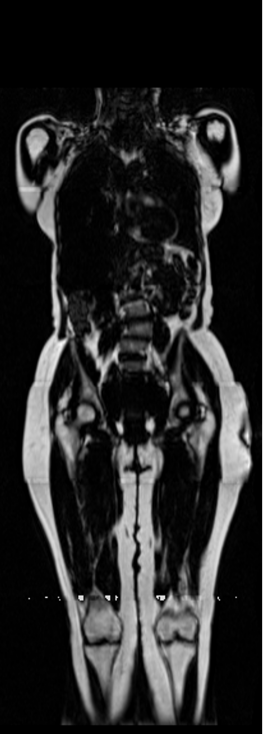

Notably, X-Diffusion achieves state-of-the-art dB for a few input slices while baselines require more than 60 input slices to achieve similar performance (Figure 7). The margin is more than 12 dB PSNR for the 1-slice input in both the BRATS and the UK Biobank benchmarks (see Table 1 and Figure 6). For reference, two randomly sampled MRIs from UK Biobank would have a PSNR of 15.95 dB 0.36 (on 4800 randomly sampled examples). Omitting the preprocessing step of alignment DXA to MRI, leads to a drop of PSNR on average by 2.87 dB (29.01 dB 26.14 dB). The slices from 3D reconstructed volumes at varying depths and axis of rotation, visually match the ground truths for both brain and whole-body scans (see Figures 4 and 5 left). We also plot the error map (Figure 3) and the spread of the error (Figure 5 right) of such X-Diffusion generations to highlight the differences with the ground truth MRIs.

Preservation of Spine Curvature. For the spine segmentation on UK Biobank, we use a UNet++ model [83] with Dice Loss. We use a model trained to predict curves on DXA on UK Biobank [11]). We measure the Pearson correlation factor [11] of spine curvature measured on the generated MRIs where the input is a single MRI coronal slice, a single sagittal slice, or from the paired DXA, against the curvature of reference real MRIs of the same samples. The correlation coefficients are 0.89 for the coronal MRIs, 0.88 for the sagittal MRIs, and 0.87 for the DXAs on the test set of 308 human-annotated angles. We can then bin the curvature of the spines under different scoliosis categories based on human-annotated angles: mild: , moderate: , and severe . We show the results in Figure 8. This illustrates that the generated MRIs preserve the spine curvature from normal to severe scoliosis cases. Additional details about spine curvature are provided in supplementary material.